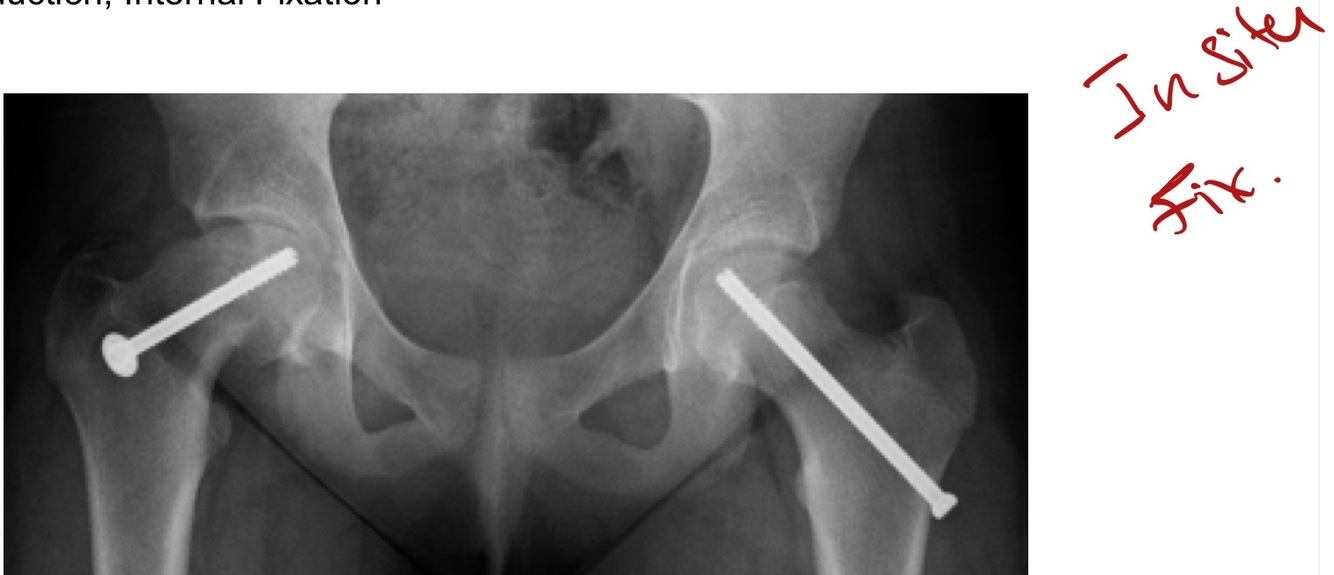

Hip Fx’s—Prox Femur

ORIF

In Situ Fixation